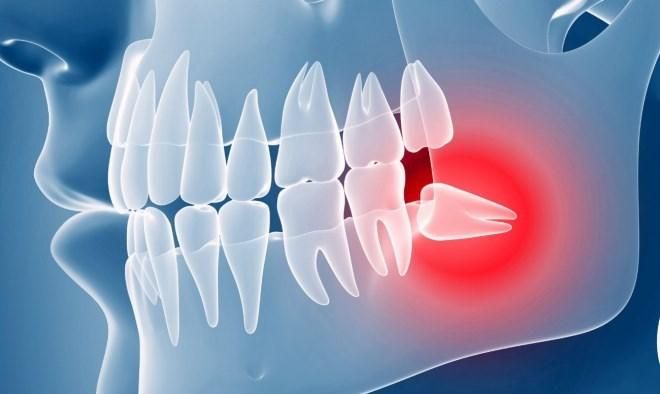

Як розповів щелепно-лицевий хірург Євген Фесенко, найчастіше зуби мудрості прорізаються у віці від 16 до 26 років. Часто такі зуби не беруть участі у жуванні.

Коли потрібно видаляти зуб мудрості:

- коли у прилеглих м’яких тканинах розвиваються гнійно-запальні процеси;

- при розвитку кіст щелепи чи пухлин від зуба мудрості;

- в разі постійного травмування (накушування) зубом мудрості слизової оболонки порожнини рота;

- за 6 місяців до операції по корекції форми нижньої щелепи;

- при скупченості зубів або зміщенні зубів верхньої та нижньої щелепи;

- коли треба запобігти перелому нижньої щелепи у людей, що займаються контактними видами спорту.

Найчастіше, зуб мудрості видаляють хірургічним шляхом через запалення слизової навколо зуба мудрості (перикороніт). Помилковим є те, що часто цей стан пацієнти розцінюють як "прорізання зуба мудрості".

Симптоми перикороніту:

- неприємні відчуття в ділянці зуба мудрості;

- додається біль при ковтанні;

- ускладнення під час відкриття рота;

- підвищення температури тіла;

- неприємний присмак у порожнині рота.